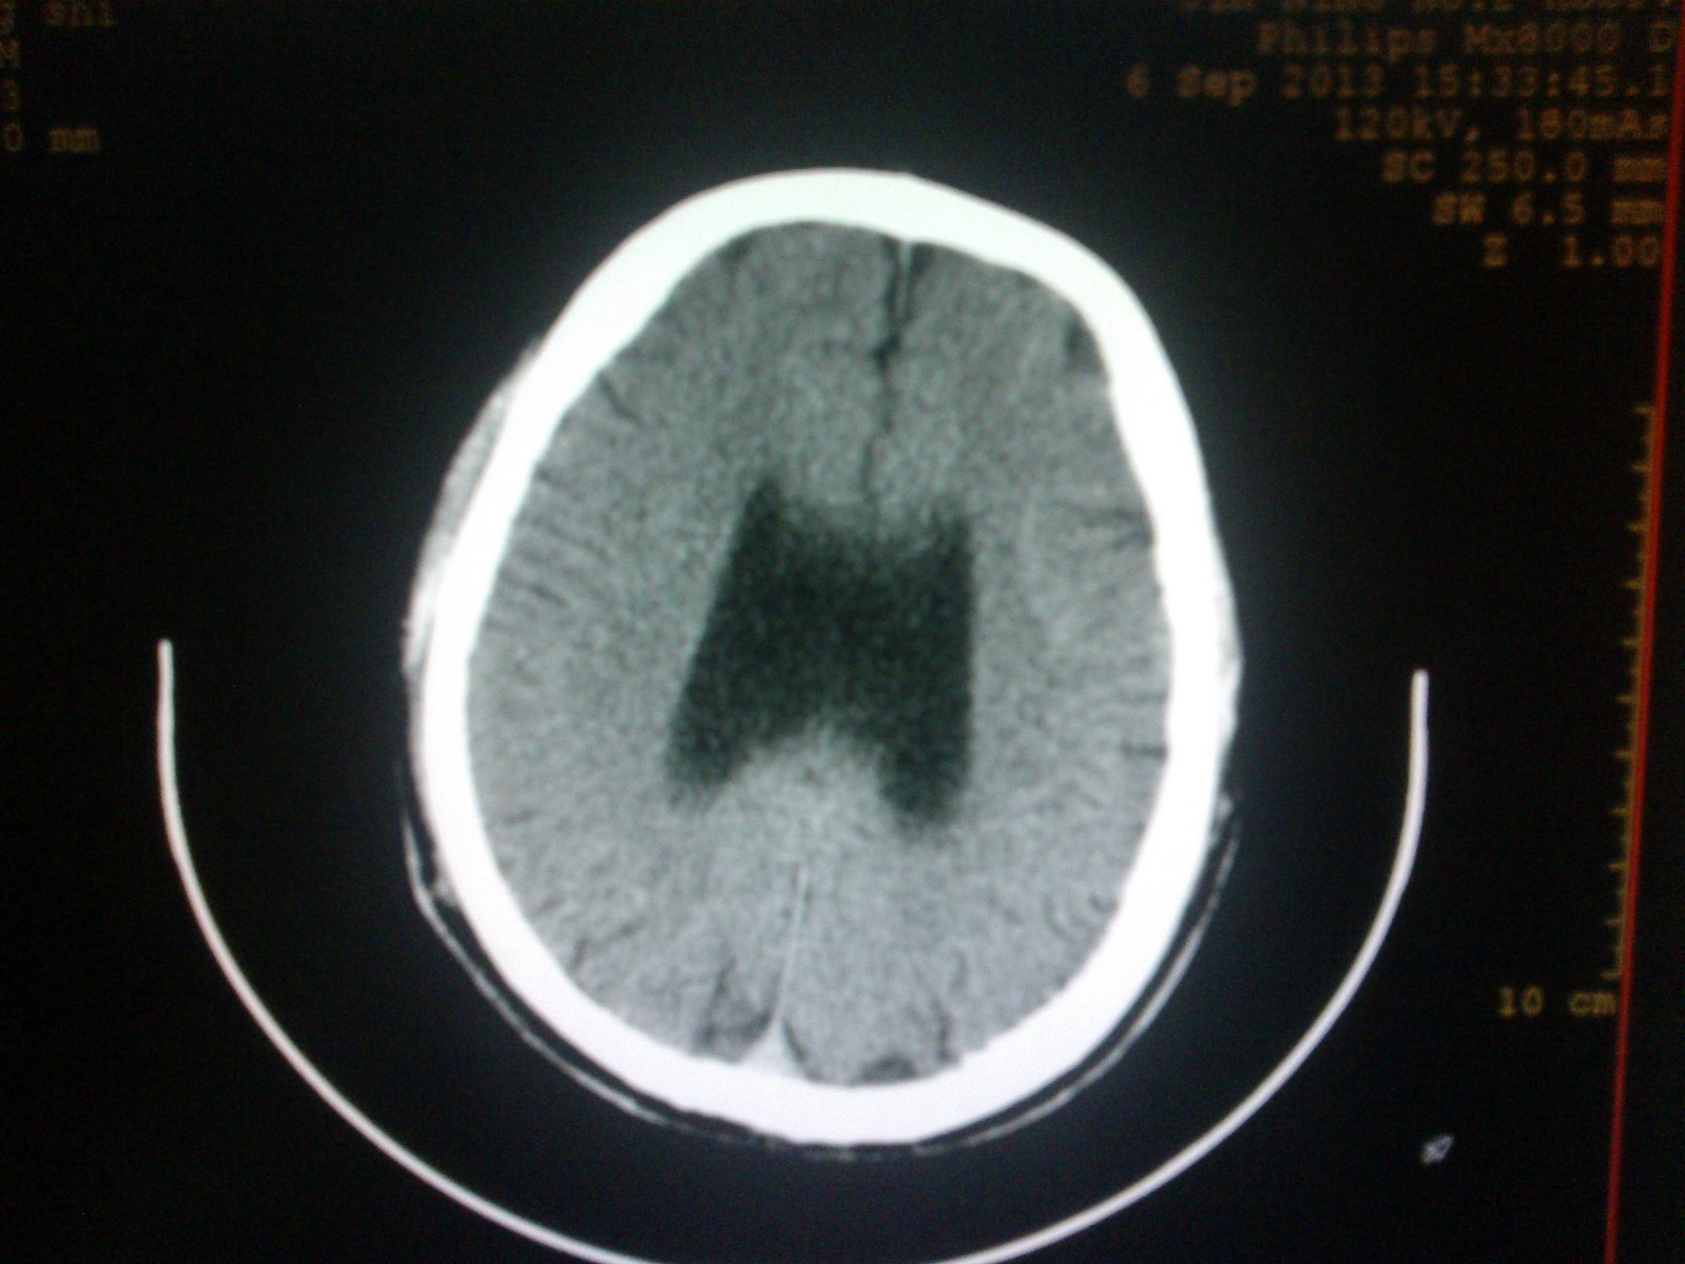

螺旋CT(SCT):螺旋CT掃描是在旋轉(zhuǎn)式掃描基礎(chǔ)上,通過滑環(huán)技術(shù)與掃描床連續(xù)平直移動而實現(xiàn)的,管球旋轉(zhuǎn)和連續(xù)動床同時進行,使X線掃描的軌跡呈螺旋狀,因而稱為螺旋掃描。